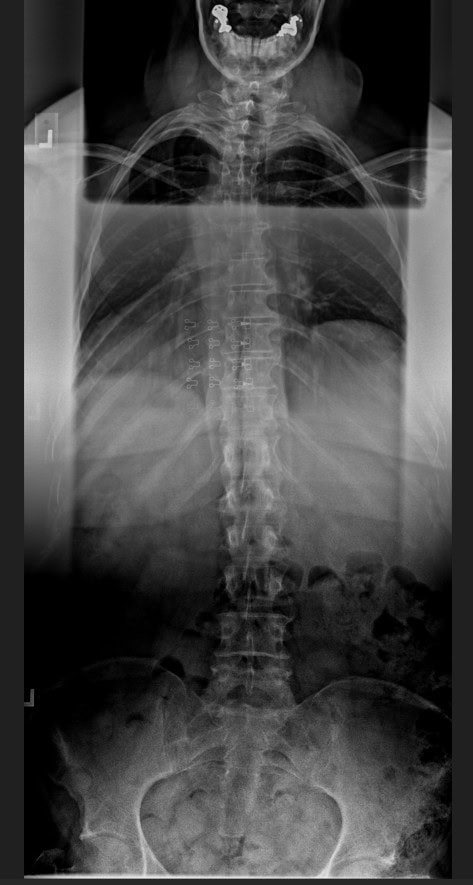

Pre Scan